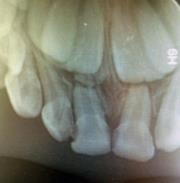

孩子門牙受外傷(shang) 後牙根變短了

牙齒外傷(shang) 通常需要及時到醫院拍片檢查牙齒情況,確定是否傷(shang) 及神經,以及是否需要做鬆牙固定等處理,還需要確定牙槽骨的等情況。

牙根折斷